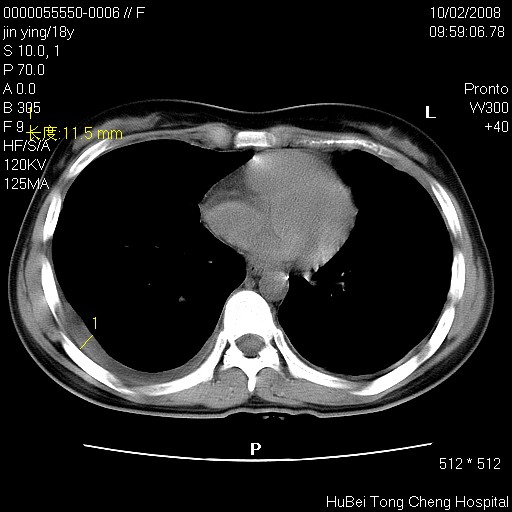

患者 女,18y。发热十余天,伴咳嗽。pe:t39⒈℃,bp 110/80mmhg,p 86次/min。神清,精神欠佳。双肺可闻及少许湿罗音。既往史不详。

临床诊断:肺部感染?

胸部ct轴位平扫(层厚10mm,螺距1.5,重建间隔10mm),图像如下: